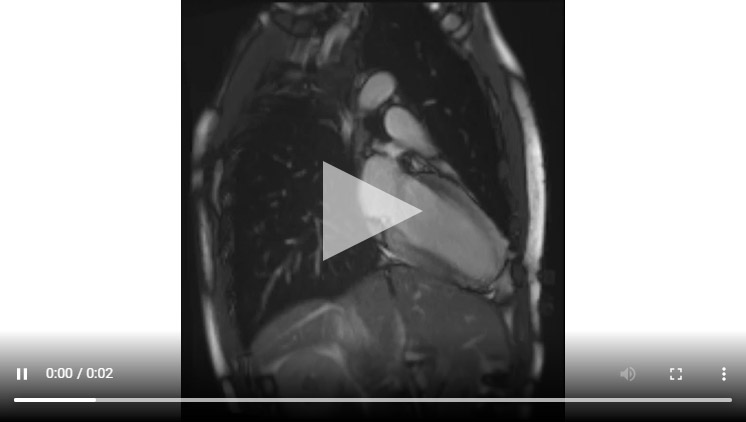

Figure 1C : Séquence Ciné-IRM coupe 2 cavités